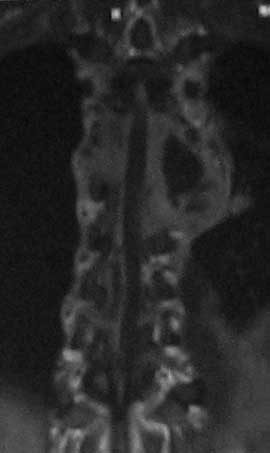

Доплнительное изображение 3. спинной мозг максимально компримирован на уровне 6 грудного позвонка.

В решении вопроса о протяженности резекции тел позвонков, считаю нецелесообразным ориентироваться на данные МРТ, в том числе на МР реконструкции, так как значительное повышение Т2 сигнала, которое мы видим на представленных снимках, появляется уже на первой неделе заболевания вследствие цитотоксического отёка и только потом некроза (С.А. Тиходеев, А.А. Вишневский «Неспецифический остеомиелит позвоночника» 2004). На представленных КТ тело позвонка (м.б. ThVI?) повреждено полностью и задние его отделы включительно, по всей видимости, этот уровень соответствует максимальной компрессии спинного мозга.